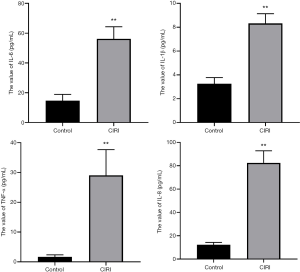

Pearson’s correlation analysis

Figure 4 shows the results of Pearson’s correlation analysis. The level of serum miRNA-183 in the CIRI group was positively correlated with the increase of imaging lesions (r=0.758, P<0.0001). R2=0.57 indicates that the regression relationship can explain the 57% variation of the dependent variable.

Increasing attention has been paid to the application of miRNA in clinical practice. The brain tissue is rich in miRNA, with more types and higher expression levels of miRNA than in other organs. The expression of miRNA in the brain is closely regulated, and the expression of miRNA has fixed sequences and regions during the development of the brain (15). When the body is geomagnetic, miR-183 exists in sense organs, and when cancer, neurological disorders, or autoimmune disorders occur, miR-183 has a higher expression in the non-sensory organs. In etiology research and target therapy, the use miR-183 and some associated factors has gradually increased for the diagnosis, prevention and treatment of CIRI (16). miR-183 also exhibits specific expression in the human and mouse cerebral cortex, affecting the development of the cerebral cortex and regulating the differentiation of nerve cells. For example, after dorsal root ganglion injury in adult rats, the expression of miR-183 was significantly decreased, and its distribution was closely related to stress granule (SG) protein, suggesting that the regulation of chronic neuralgia by miR-183 could be realized through pain-related genes (17). Yuan et al. (18) found that miR-183-5p increased in the hippocampus under chronic and persistent mild mental stress, indicating that the increased miR-183-5p level was associated with stress-induced depression. Meanwhile, miR-183 was demonstrated to interfere with glucose and lipid metabolism, and its abnormal expression has been related to metabolic diseases like obesity and diabetes, and it has been shown to induce cerebrovascular diseases, such as atherosclerosis (19). In this study, RT-qPCR detection found that, compared with the control group, the level of miR-183 in peripheral blood of patients with CIRI was significantly higher than that of the control group. Meanwhile, the level of serum miR-183 in the CIRI group was positively correlated with the increase of imaging lesions. These results confirm that miR-183 is involved in the occurrence and development of ischemia-reperfusion. MiR-183 can inhibit the activation of microglia and the expression of inflammatory factors through NF-κ-signaling pathway (20). Down regulation of miR-451 can promote angiogenesis by targeting macrophage migration inhibitory factor in hypoxic human umbilical vein endothelial cells, indicating that miR-451 is a potential candidate for the treatment of cerebral ischemia injury (21). SNHG1 targets miR-199a and up regulates SIRT1 expression, thus alleviating cerebral ischemia/reperfusion injury through AMPK pathway activation (22).